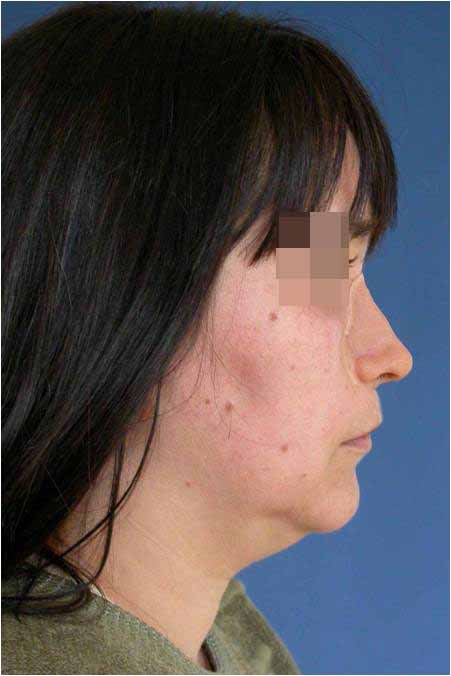

Лицева корекция преди и след лечението – случай на доц. Джоров